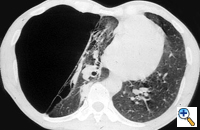

| Figure 3: Chest x-ray of a large bulla with true infection; after the appropriate medical treatment fever, hemptysis and fluid level persisted and the bulla was resected. |

Surgery is generally indicated to modify the functional status of the underlying lung by (1) relieving restrictive changes; (2) increasing compliance and airway caliber; (3) improving V/Q ratio; and (4) decreasing the physiologic dead space. These goals are easy to obtain in patients with enlarging bullae and minimal underlying lung disease. These are the best candidates for surgery and optimal results can be expected. Surgery is also indicated to treat complications related to the bullae, such as pneumothorax, true infection (Figure 3), hemoptysis, cancer (Figures 4, 5), and pain.